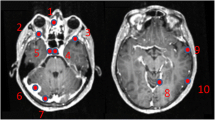

Example of two patients with concordant imaging results (A) and incremental diagnostic value of [18F]FET-PET (B). A Example of a patient (#10) with an anaplastic astrocytoma WHO grade III who was treated with combined radiochemotherapy prior to PET. Axial T2WI and T1WI + CE depict the tumor in the left thalamus and insular region (red arrows); axial PET shows high uptake of [18F] FET in these regions (white arrows). Both MRI and PET identified correctly the tumor recurrence. B Example of a patient (#19) with a pilocytic astrocytoma who was treated with surgery and chemotherapy prior to PET. Axial T2WI and T1WI + CE show cystic as well as contrast enhancing lesions next to the surgical cavity consistent with both unspecific changes and tumor recurrence (red asterisk); in contrast, axial PET demonstrates focal high uptake of [18F]FET (white asterisk)